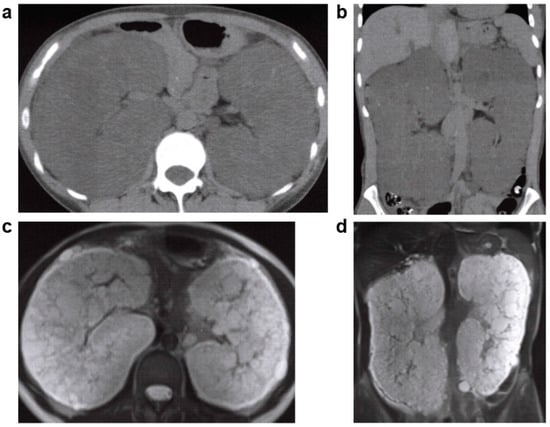

2.5. Unilateral Renal Cystic Disease (URCD)